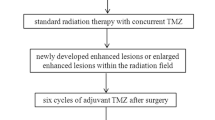

This study was approved by the institutional review board (IRB), which waived informed consent. A total of seventy-three AA patients who had undergone preoperative DCE and DSC MRI and received standard treatment, including partial resection or biopsy followed by radiation therapy, were included in this retrospective study. Based on Response Assessment in Neuro-Oncology (RANO), patients were sorted into progression (n = 21) and non-progression (n = 52) groups. Tumor boundaries were defined as high-signal intensity (SI) lesions on fluid-attenuated inversion recovery (FLAIR) imaging, where we analyzed mean pharmacokinetic parameters (Ktrans, Vp, and Ve) from DCE MRI and contrast leakage information (mean extraction fraction (EF)) from DSC MRI.